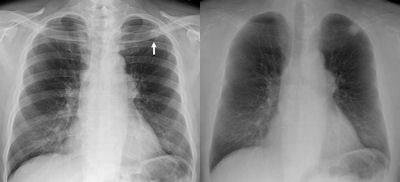

| Standard PA chest radiograph (left) shows a nodule in the left upper lobe (arrow), partly obscured by overlying bones. Dual-energy subtraction image (right) provides more complete bone subtraction, but requires specialized equipment. |

Dr. Reginald Munden, chairman of radiology for the University of Alabama at Birmingham (UAB) Health System, has found that CT is often avoided when dual-energy imaging determines that a suspicious mass is a calcified granuloma.

"If dual-energy indicates that, then I'm finished," Munden said in an interview. "We don't need to anguish over what that nodule is."

The potential diagnostic advantages of digitally subtracting bone from soft tissue have been known since research conducted in the early 1990s. Dr. John H. M. Austin at Columbia University Medical Center in New York City, for example, showed that 81% of missed lung cancers were partially obscured by ribs and clavicles (Radiology, January 1992, Vol. 182:1, pp. 115-122).